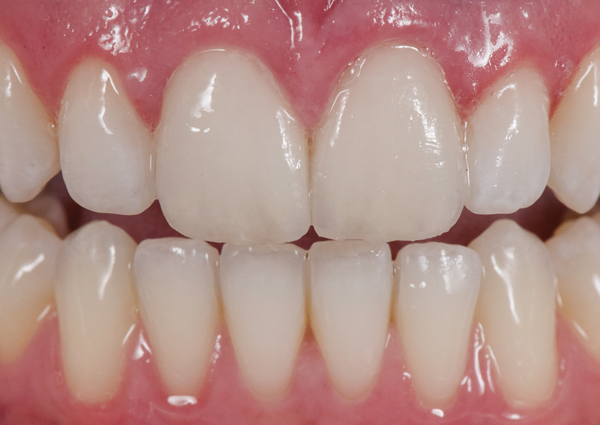

Fig 3. Preoperative (Fig 1), preparation (Fig 2), and final postoperative (Fig 3) images of a two-unit CL-I feldspathic veneer case.

Figure 3

Fig 5. Preoperative view of patient requiring esthetic changes up to at least the bicuspids.

Figure 5

Fig 6. Postoperative view with CL-I feldspathic porcelain veneers up to the first bicuspid.

Figure 6